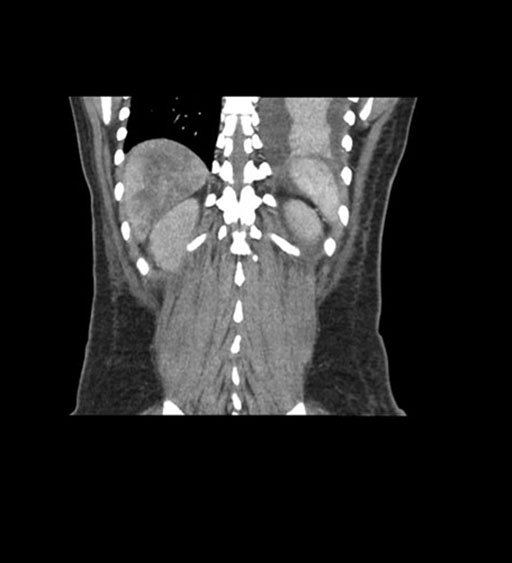

Coronal Arterial

Coronal Venous